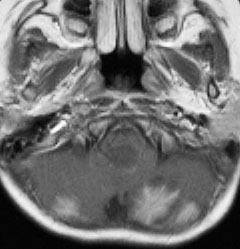

- MRIで診断します

- 境界がはっきりした腫瘍です,くりんとしています

- ガドリニウム造影剤で白く映ります(増強される)

- でも,ガドリニウム造影剤が入らなくて白く映らないものもあります

- 周囲の小脳が腫れることが多いです(脳浮腫)

典型的な小脳虫部(小脳の真ん中)の髄芽腫です。横の方,ルシュカ孔へ伸びていないので上衣腫と区別できます。ガドリニウムという造影剤で白く写っています。